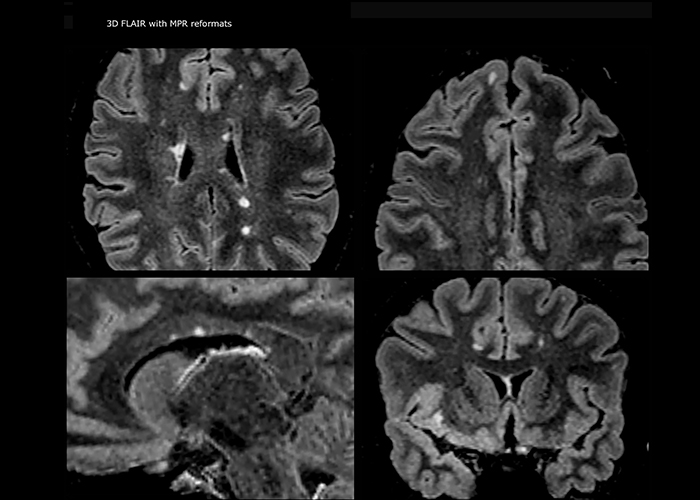

“Ingenia 3.0T provides us very good image quality with high SNR, even if we push the resolution. For example, in FLAIR images we may have an isotropic resolution of 0.9 mm. Ingenia allows us to use 3D T1 TSE with BrainView, which has a better sensitivity than 2D spin echo imaging[2] and 3D gradient echo imaging. Ingenia also provides highly reproducible exams, which is important in MS imaging so that follow-up exams at different time points are done the same way.”

For MS imaging in the brain, Dr. Savatovsky uses 3D FLAIR as the basic sequence to visualize the lesions and assess the situation and lesion load. “We count the lesions in each location to determine if the criteria of the disease are fulfilled. We use a T2-weighted sequence because our neurologists are used to it. We compare the lesion load on FLAIR with a 3D T1 post-contrast sequence to help us determine whether lesions are old or new. We typically administer the contrast before the patient enters the machine because it shortens the examination time and allows to visualize active lesions that tend to be more visible after several minutes. When a differential diagnosis is difficult, we add sequences such as susceptibility imaging, because some focal MS lesions have a small vein in the center[3].”